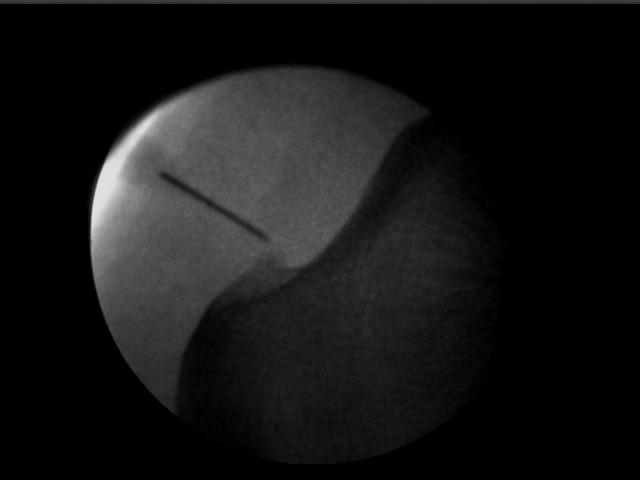

- Infiltración en Fascia Plantar